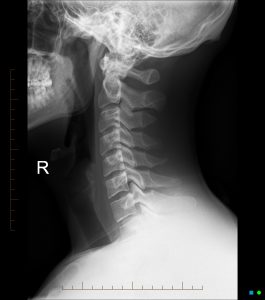

Near Normal Spine

This side-view X-ray shows what we call a "near normal" cervical spine. The patient is facing to the right, allowing us to view the natural forward curve of the neck, which acts as a shock absorber. The disc spaces between C2 and C7 appear thick and even, and the vertebral bodies have clean, square shapes with well-defined borders — all indicators of a healthy spine.

When subluxations occur and remain uncorrected, predictable patterns of degeneration begin. These changes affect spinal structure, nerve function and overall health, gradually progressing into more advanced phases.